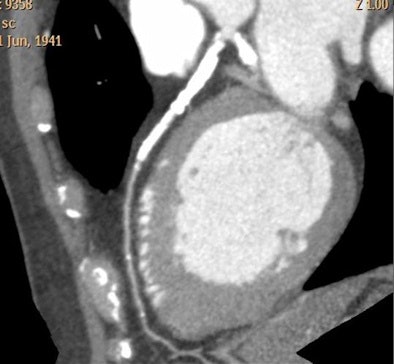

|  |

| CTA interpretation is complicated by heavy coronary artery calcification; flow analysis could potentially aid diagnosis in such cases. All images courtesy of Dr. Henning Bovenschulte. |